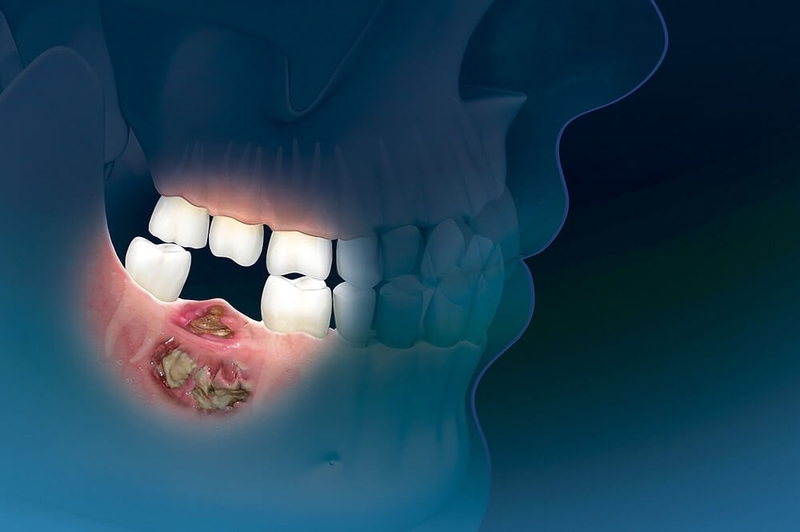

Bệnh hoại tử xương là tình trạng các tế bào mô xương chết dần cho nguồn cung cấp máu nuôi bị gián đoạn tạm thời hay vĩnh viễn. Đây được cho là nhóm bệnh hoại tử vô mạch hay hoại tử vô trùng. Hoại tử xương hàm là tình trạng hoại tử xương xảy ra ở xương hàm - xương di động duy nhất ở hộp sọ con người. Khi các tế bào mô xương hàm không được cung cấp máu nuôi đầy đủ sẽ yếu dần đi và dẫn đến hoại tử.

Một số bệnh nhân bị bệnh hoại tử xương hàm do sâu răng nhưng không được điều trị sớm. Sau một thời gian răng sâu, vi khuẩn xâm nhập vào tủy răng gây viêm tủy xương hàm dẫn đến các biến chứng nguy hiểm trong đó có hoại tử xương hàm.